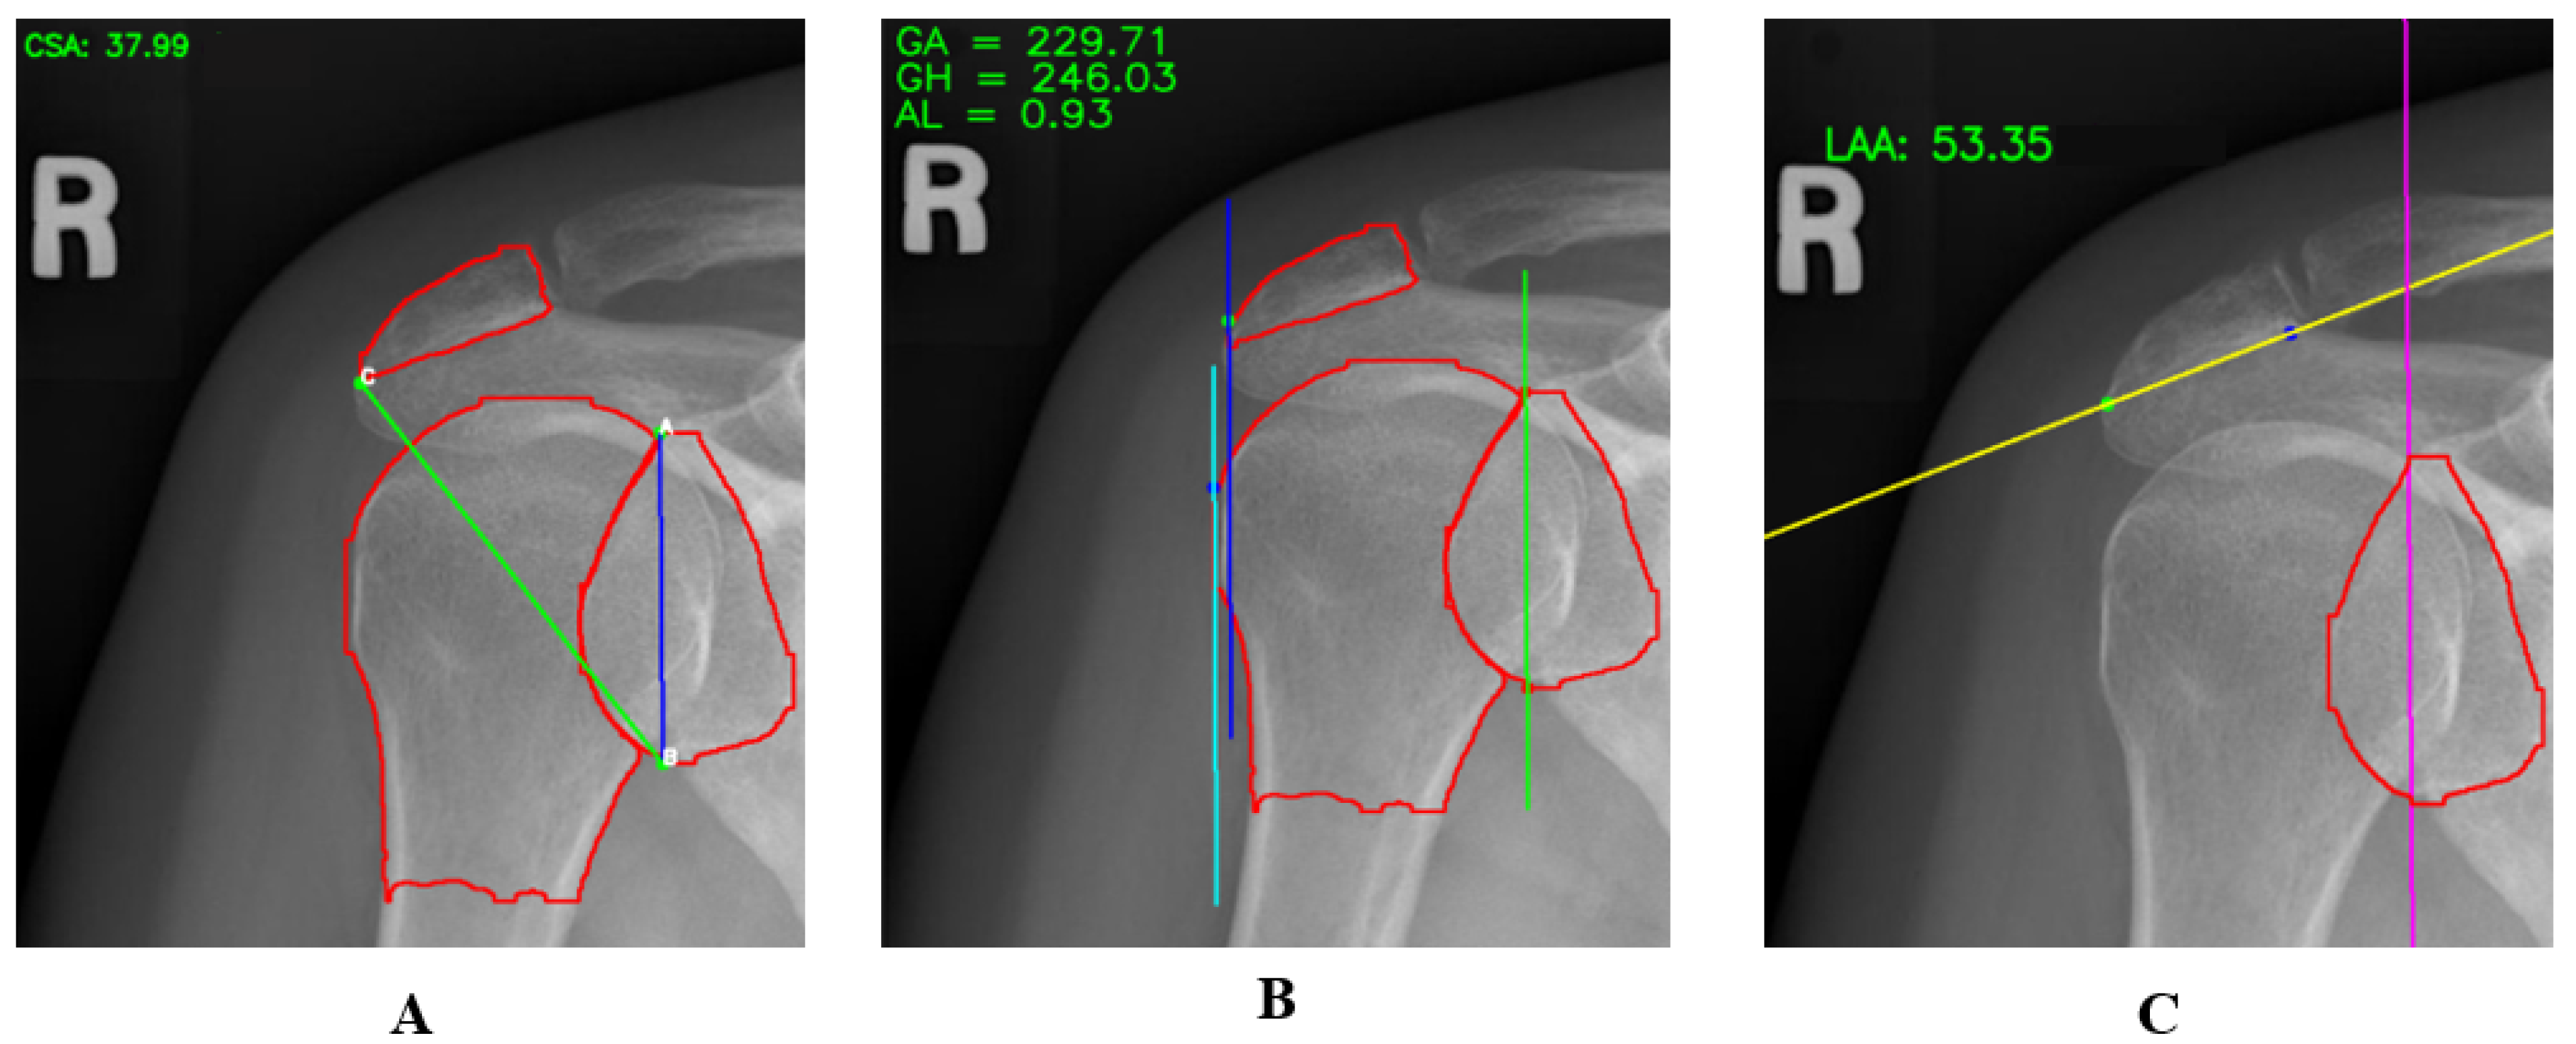

Table 2 shows the distribution of CSA, LAA, and AI values among individuals, which is important for understanding the structural features potentially associated with shoulder pathologies. Individuals with CSA values below 30 generally exhibit a lower risk of disease, while those with values between 30 and 35 degrees may have a moderate risk. CSA values above 35 may indicate a high risk and are often associated with issues such as shoulder impingement syndrome and rotator cuff tendinitis [24]. Individuals with an LAA value less than 45 degrees generally have a moderate to low risk, while values between 45 and 55 degrees are considered normal. LAA values above 55 are associated with a high-risk group and are commonly linked to rotator cuff pathologies [25]. AI values reflect acromion width; individuals with AI < 0.7 typically have a moderate to high risk, which may indicate pathological effects of a narrow acromion. Those with AI values between 0.7 and 1 have a normal risk level, while individuals with AI ≥ 1 have a wider acromion, which may increase the risk of shoulder pathologies [26]. Considering these values in clinical assessments is crucial for better understanding and managing potential issues in the shoulder joint. Table 3 also shows the mean, standard deviation, minimum, and maximum values for CSA, AI, and LAA. Figure 4 shows the measured CSA, AI, and LAA values on example images. The segmented acromion, glenoid, and humerus are shown in red. AI is a distance, while CSA and LAA are angles.

Figure 4. Example images showing the measured values of CSA (A), AI (B), and LAA (C).